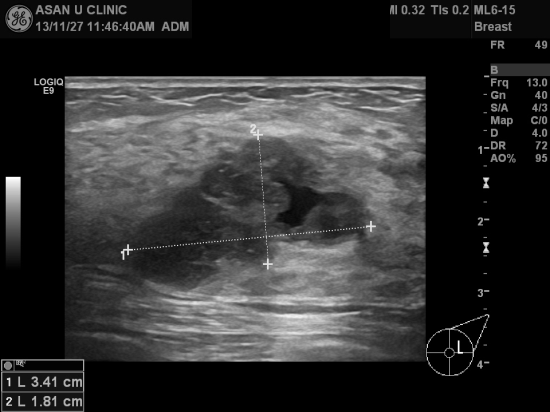

좌측유방의 몽우리와 오렌지빛 유두분비물을 주소로 내원한 35세 여자 환자분입니다.

본원 초음파 검사상 좌측유방에 3.41cm의 결절과 1.32cm의 결절이 있었고

두개 다 침윤성 유방암으로 각각 진단되셨습니다.